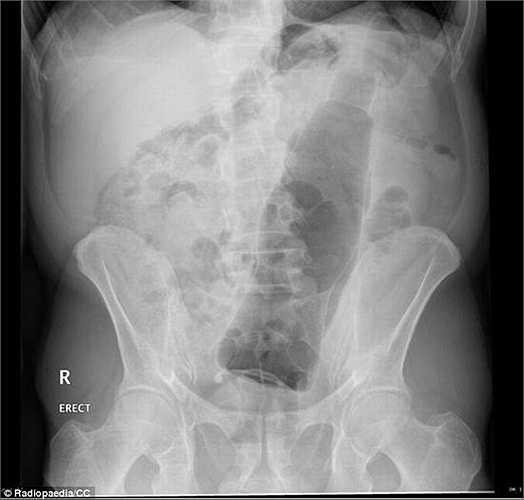

Các nhân viên y tế không thể nhịn cười khi hình ảnh X-quang cho thấy trong hậu môn của bệnh nhân là một chai nước ngọt.